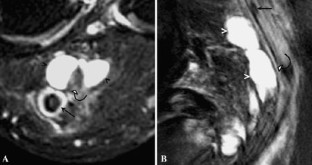

Figure 2